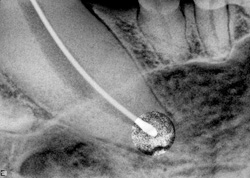

The canal obturation is complete and the canal has been back filled with sealant and additional gutta percha cones. (Photo courtesy of Dr. D.H. DeForge)